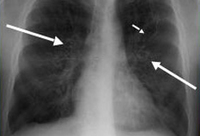

Aspergilose broncopulmonar alérgica

Radiografia torácica em um paciente com aspergilose broncopulmonar alérgica (ABPA): as sombras em forma de anel (setas longas) representam as vias aéreas bronquiectásicas observadas na seção transversal; em trilho de trem (setas curtas) observadas longitudinalmente

Do American College of Chest Physicians, PCCU Volume 17, Lesson 17: Allergic bronchopulmonary aspergillosis; usado com permissão